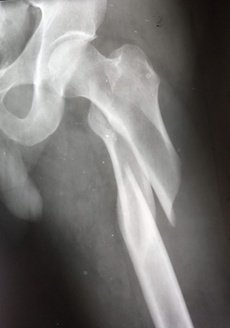

При огляді: положенння хворої пасивне на каталці, хвора вказує на біль в області лівого кульшового суглобу що посилюється при пальпації та спробі рухів у суглобі. Ліва н\кінцвка ротована до зовні. Позитивний симптом «прилиплої п’яти». Вкорочення лівої н\к до 3х см. Проведено рентгенографію лівої стегнової кістки з кульшовим суглобом. Встановлено діагноз: Закритий трансцервікальний (Клас АО 31.В2) зі зміщенням.

Хвора госпіталізована в травматологічне відділення для подальшого дообстеження та оперативного лікування з тимчасової фіксацією лівої нижньої кінцівки для зменшення больового синдому. В умовах травматологічного відділення хвора була дообстежена та оглянута суміжними спеціалістами терапевтом, кардіологом, анестезіологом.

Протягом 28 годин від отримання травми хвора була прооперована. Геміартропластика лівого кульшового суглобу. Після оперативного втручання хвора перебувала під наглядом у відділенні інтенсивної терапії. На 2гу добу хвора переведена в травматологічне відділення. В травматологічному відділення хворій під наглядом лікуючого лікаря було дозволено сідати у ліжку. На 3 тю добу хвора під наглядом лікуючого лікаря з допомогою вставала та пересувалася біля ліжка в палаті. На 5 ту дому після оперативного втручання хвора самостійно пересувалася в межах травматологічного відділення. На 12 добу хворій було знято шви з рани. Хвора в задовільному стані виписана, і самостійно залишила лікувальний заклад. Надано рекомендації з приводу подальшого лікування в амбулаторних умовах.